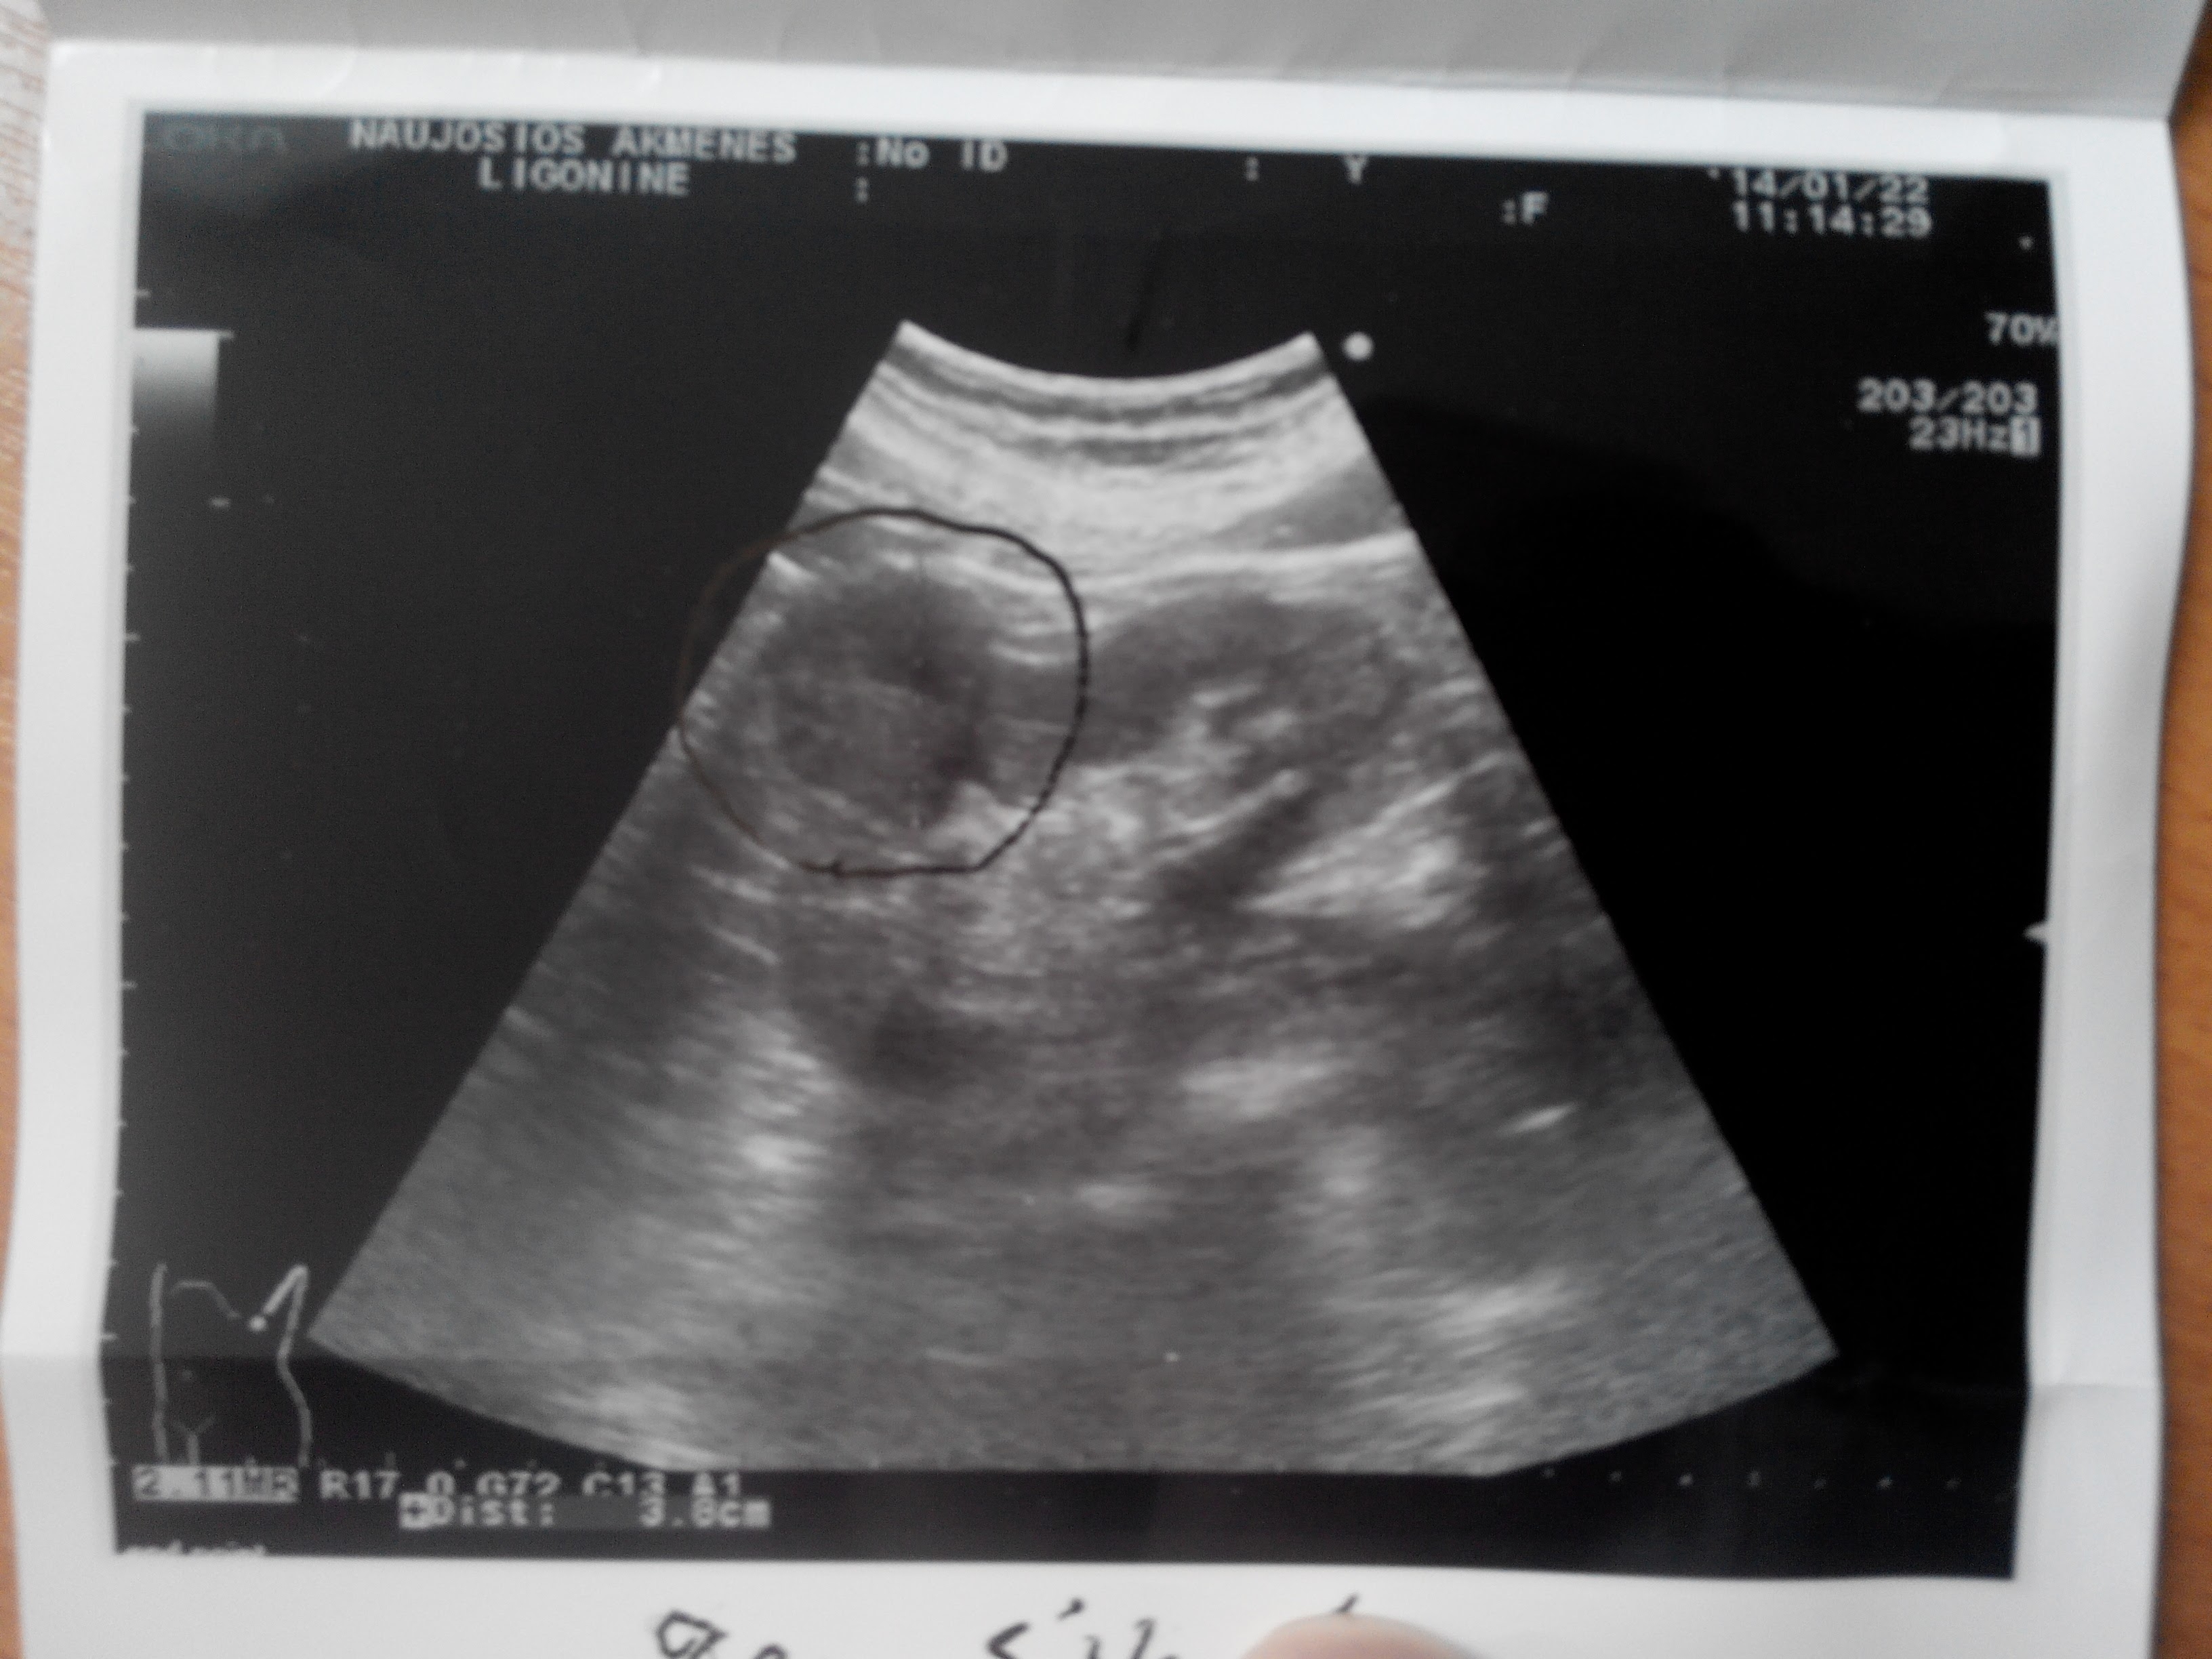

Рубец почки послеоперационный

Пациент оперирован по поводу опухоли почки, выполнена ее резекция.